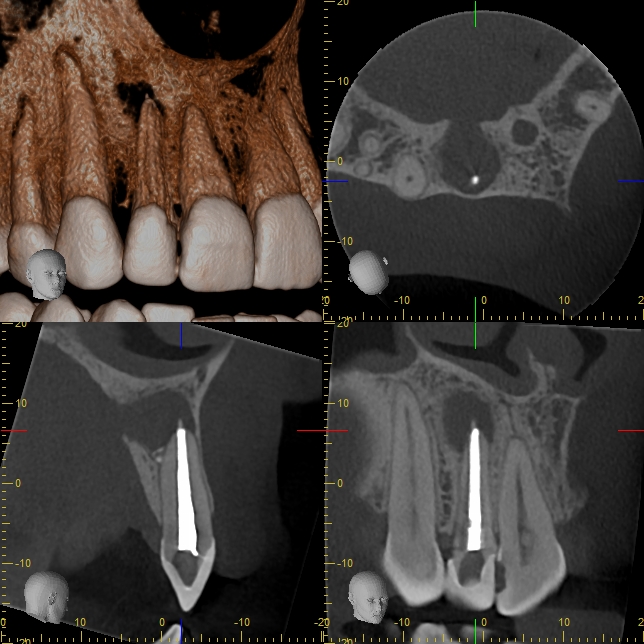

XYZView_20171123_113539 Veröffentlicht 19. Januar 2018 am 644 × 644 in Immer schön skeptisch bleiben 2